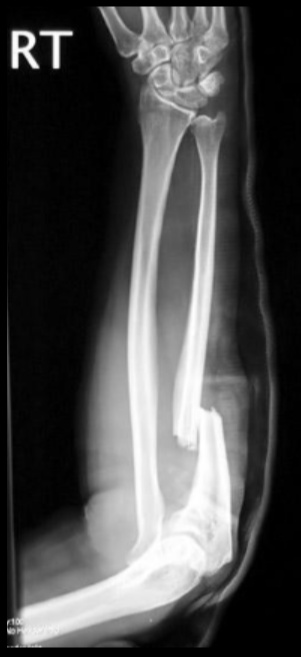

Monteggia

Forearm injury involving a fracture of the proximal third of the ulna with concurrent radial head dislocation, which is more common in children than adults.

.,

Monteggia fractures are typically the result of a fall onto an outstretched hand, or more frequently a trauma. A classic mechanism is called the night-stick fracture, which produces the fracture when a patient guards against a strike using the ulnar side of their forearm.

Patients with a Monteggia fracture will present with pain and swelling at the elbow joint, which may or may not show obvious dislocation.

Most Monteggia fractures in children are treated with a cast, but most adults are treated surgically.

A major complication of Monteggia fractures is compartment syndrome, which is a rise in intracompartmental pressure that impedes blood flow.